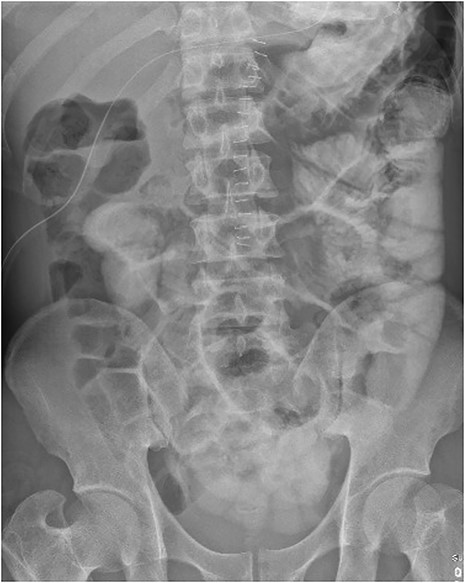

On examination in the emergency department, he was found to have localized peritonism to the epigastrium and was diaphoretic. An urgent erect chest radiograph (Figs 1 and 2) was revealing of gross pneumoperitoneum, presumably of a hollow viscous perforation as the source. General surgery was consulted after the presence of free air was detected. In the setting of the patient’s virgin abdomen and unremarkable surgical history, with peritonism and free intraperitoneal gas, the patient proceeded directly to urgent exploratory laparotomy with concurrent resuscitation measures, including intravenous fluid resuscitation and placement of an indwelling catheter.